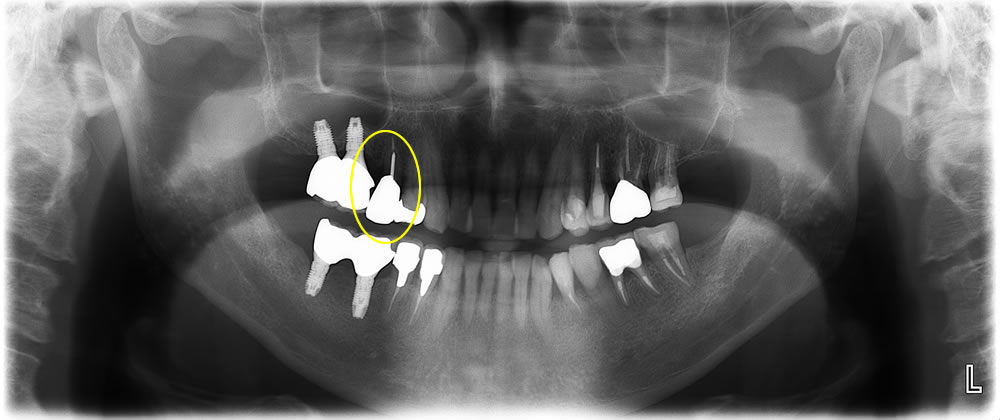

かぶせ物が取れた歯を抜歯即時埋入インプラントで治療した症例

こちらの患者さまは、左上奥歯のかぶせ物が取れて食事がしづらいとの主訴で来院されました。当該歯の診査・診断の結果、保存不可能と判断し、患者さまと相談の結果、抜歯即時埋入インプラントにて咬み合わせを回復する計画を立てました。

抜歯即時埋入インプラント治療の実施/治療完了

当該歯を抜歯し、即日にインプラントを埋入。当該歯の骨量が少なかったため、CGFを用いた骨造成法を併用しました。インプラントと顎骨の結合までの待機期間を経て、最終的な上部構造を装着して治療完了です。しっかり噛めるようになり、何でも食べられるようになったと患者さまにも満足いただけました。

| 年齢・性別 | 60代男性 |

|---|---|

| 治療期間 | 約5ヵ月 |

| 治療費(税込) | プレミアムインプラント 495,000円 骨造成法 55,000円 CGF 11,000円 |

| リスク・注意点 | ・日々のケア、定期メンテナンスを怠るとインプラント周囲炎になり、インプラントが脱離する可能性がある。 ・骨量によっては骨を作る処置が必要になったり、治療自体ができない場合があります。 ・糖尿病など、全身状態によっては治療が受けられない場合があります。 |